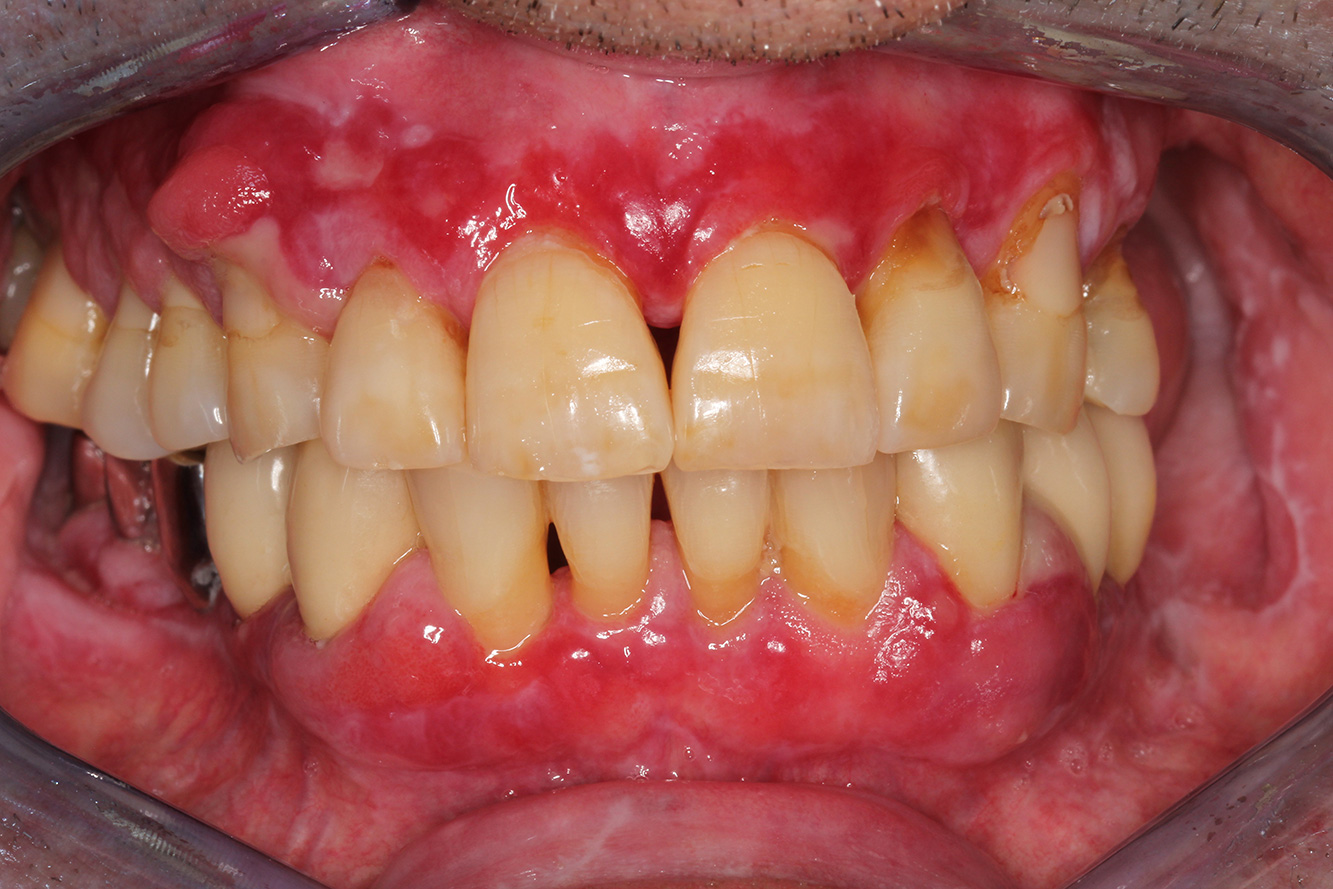

A 71-year old patient presents with having previously undergone a kidney transplant and with a history of hypertonia (high blood pressure). Due to his medical history, long-term medication with cyclosporine is required to suppress the immune system, as well as amlodipine to lower blood pressure. The patient also reports sensitive and bleeding gums. From an oral health perspective, the patient has undergone dental restoration and has eight missing teeth, pronounced gingival growth, and grade B, stage II periodontitis with active pockets and initial root caries on tooth 22. The caries risk assessment determines a moderate risk of caries (API 60). The following treatment recommendations can be determined for the prophylaxis session.

Based on the patient’s medical history, it is possible to identify a particular risk of complications. Due to the kidney transplant, the patient is immunosuppressed (cyclosporine), and therefore has a weakened immune system and requires infection prophylaxis (recommendation: 2 g of amoxicillin as an antibiotic, 1 hour before the session). At the same time, the patient’s long-term medication carries an increased risk of disease, as the gingival overgrowths identified are associated with this medication (20).

The patient’s situation must be addressed, especially when it comes to motivation and instruction. Due to the gingival overgrowths, the patient finds it difficult to practise good oral hygiene at home. The increased susceptibility to infection as well as the progression and emergence of the overgrowths (22) should be discussed at the patient’s level. At the same time, the patient should be instructed in hygiene techniques that are tailored to his individual needs.